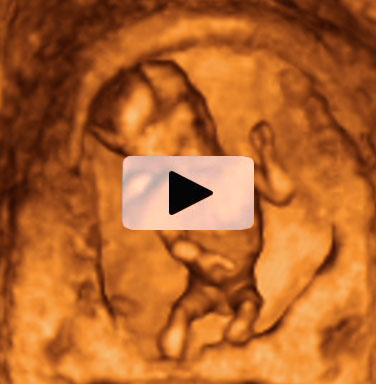

Bebé de 12 semanas de embarazo en una ecografía 3D que muestra un plano rotatorio. El feto está apoyado en las paredes de la cavidad uterina materna. El especial corte de este ultrasonido hace que la imagen parezca una escultura.

Ecografía 3D de un feto de 12 semanas en rotación

Es impresionante ver a este bebé de doce semanas de gestación en este plano rotatorio del útero materno. La sensación de volumen que produce hace que parezca una escultura. El pequeño está apoyado en la paredes uterinas y se tapa la cara con los puños en un gesto fetal característico. Se perfila bien la cara y el tronco del feto, así como el cordón umbilical. Sin embargo, las piernas aparecen más desdibujadas en el vídeo. Este corte de la imagen puede ayudar en el diagnóstico de alguna patología, aunque muchas otras veces se da como recuerdo para la embarazada.